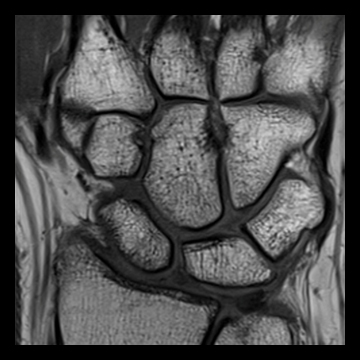

手・指関節

PD TSE,

PD TSE SPAIR,

T1 TSE

TNATIVE SPACE非造影